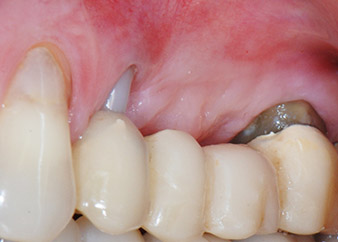

A 58-year-old female patient complained of pain and increased mobility of her bridge abutment tooth 24. Periodontal inflammation was present with pocket depths of 7 mm mesiobuccally and more than 12 mm distally, as well as third-degree furcation involvement. Moreover, the radiograph revealed an extensive periodontal lesion around the apical region of the (alio loco) endodontically pretreated tooth 24 (Fig. 1).

One year earlier, teeth 25 and 26 had been extracted due to trauma and for endo-perio reasons, prior to the placement of the bridge. A combined endo-perio lesion was diagnosed for tooth 24, of unclear aetiology. The patient wanted to keep her bridge abutment teeth 24 and 27 and would not accept a final, or even temporary, removable prosthesis. Therefore, it was agreed to make all efforts to retain both teeth, in spite of their poor prognosis as based on radiological and clinical findings.

Placement of two submerged implants was planned at sites 25 and 26, in a surgical session with open periodontal debridement and apicoectomy of tooth 24. Due to the vertical bone deficiency at the future implant site, an internal sinus augmentation was also planned.